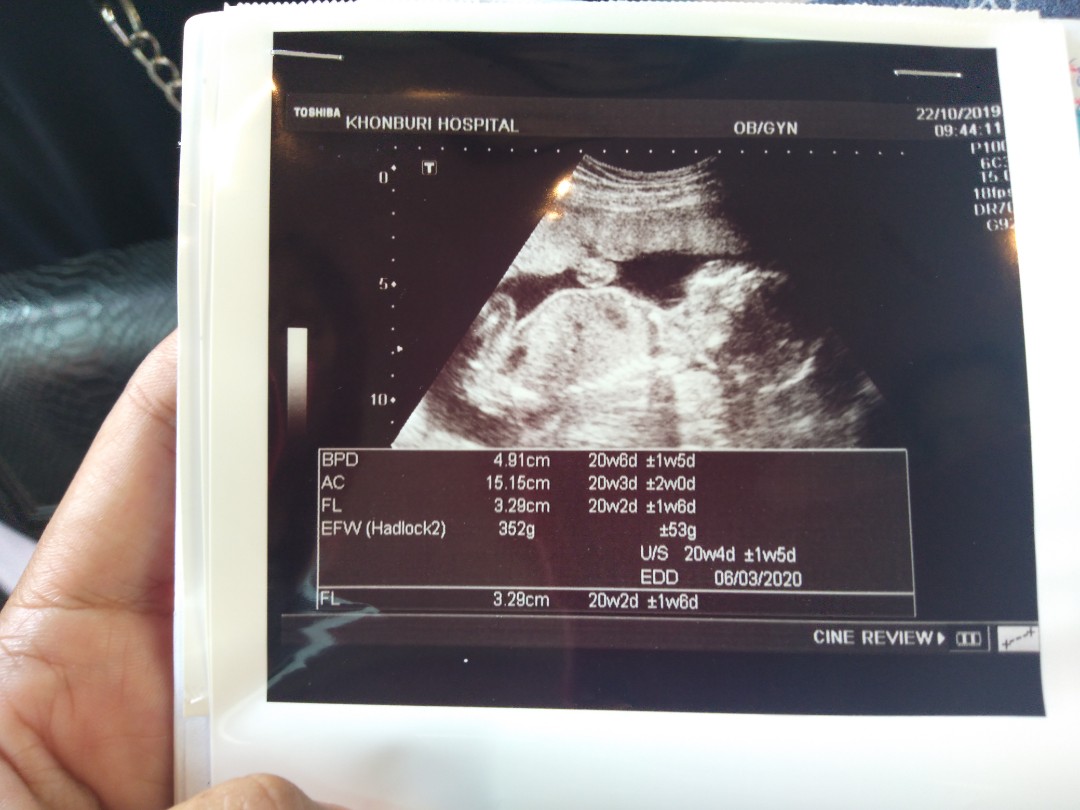

5เดือนคับผม

5 เดือนค่ะ 😍😍

5เดือนค่ะ